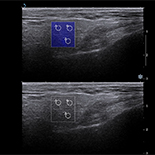

Shear wave elastography (SWE) is widely used in breast, liver, prostate and thyroid evaluations. Elastography provides additional information if used to assess parotid gland pathology. We assessed parotid glands by means of SWE to compare the parenchyma properties in different types of inflammation.

Prospective analysis included 78 consecutive patients with parotid gland pathology: sialolithiasis (33), Stensen’s duct stenosis (15), chronic inflammation (10), and primary Sjögren syndrome (pSS) (20) treated at the Department of Otolaryngology, Head and Neck Surgery of PUMS. The primary predictor variable was type of parotid pathology, and secondary predictor variables were patient age and the duration and intensity of complaints. Ultrasound pictures were compared with elastography values of parotid parenchyma.

Mean elasticity values for pSS (111 Kilopascals (kPa), Stensen’s duct stenosis (63 kPa), sialolithiasis (82 kPa), and chronic inflammation (77 kPa) were significantly higher than the mean value for healthy patients (24 kPa). Elasticity increased proportionally to the intensity of complaints: mild (51 kPa), moderate (78 kPa), and strong (90 kPa). Increased elasticity did not correspond with ultrasonographic pictures. In pSS the parenchyma was almost twice as stiff as in chronic inflammation (p=0.02), although subjective complaints were mostly mild or moderate, and the ultrasonographic picture did not present features of fibrosis.